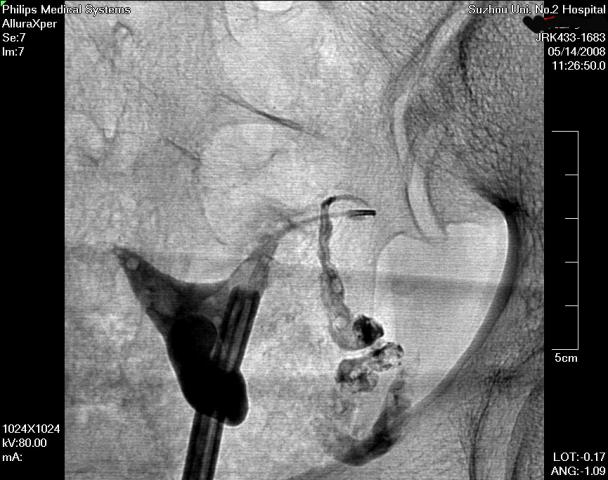

在清晰的DSA(数字减影血管造影机)的同步监测,采用同轴导管系统,进行输卵管选择性造影和再通术,主要适用于输卵管阻塞于间质部及狭部的不孕症患者,各段输卵管阻塞均可行选择性输卵管造影、通液。主要采用导管扩张术,插入导管导丝,利用导管导丝的推进扩张分离作用和造影剂的冲击力等,使输卵管疏通至伞端。手术安全高效,痛苦小,无需住院,复通率及术后妊娠率均较高。(见图1术前HSG宫腔形态正常,双侧输卵管不显影、图2左侧输卵管顺利通过导丝后造影剂通过畅、图3右侧输卵管通过导丝后畅)